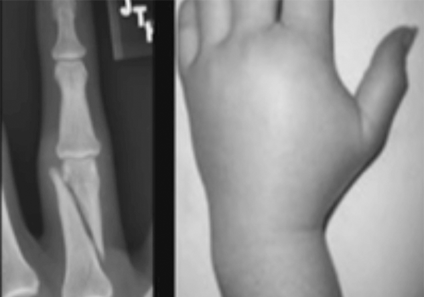

Els traumatismes en dits i mans són les lesions més freqüents en els serveis d’urgències. Lesions esportives, laborals…

Son també lesions molt comunes. Un dels mes freqüents és el lligament col·lateral cubital en el polze.